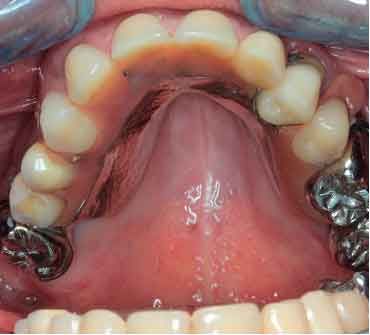

66 years old patient. Wishes to regain functional comfort and improve aesthetics.

Complaints :

- Lack of stability of his removable prosthetics

- Difficulties in eating

- Sagging of the upper lip

The periodontal structures of the remaining teeth are no longer sufficient. An edentulism is considered. The treatment plan is directed towards a removable maxillary complete prosthesis and an implant-supported mandibular complete prosthesis.

Picture - Initial bite situation

Before acquiring the CBCT, I added 2 pieces of composite to the mandible to be able to do the picking process during jaw motion recording. This is a useful trick to remember in a situation of lacking teeth.